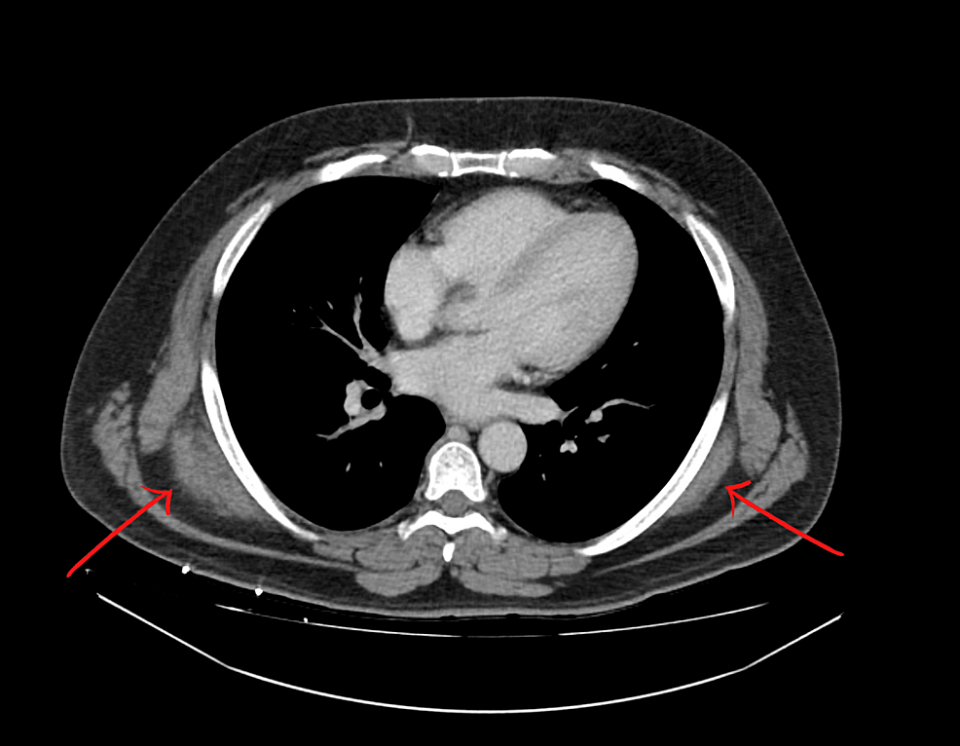

CT scan of the chest with IV contrast showed bilateral soft tissue masses present in the upper back immediately deep to the trapezius and latissimus dorsi muscles and posterior to the serratus musculature (Figure 1). On the right, the mass measured 7.3 x 3.1 x 6.5 cm. On the left, the mass measured 6.8 x 1.3 x 5.6 cm. The CT scan findings were reported as consistent with ED